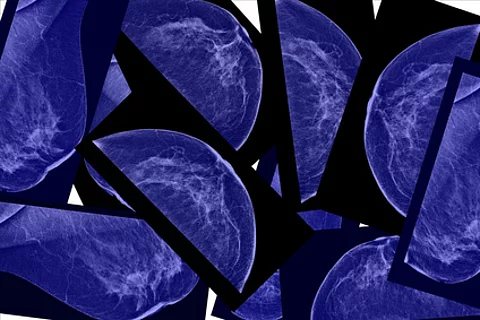

BI-RADS bei BrustkrebsGeschulter Radiologenblick sagt Histologie voraus

Die Brustkrebssterblichkeit lässt sich dank besserer Diagnosemöglichkeiten drastisch senken – und das ist nicht nur den bildgebenden Geräten zu verdanken. Vielmehr spielt der menschliche Faktor eine große Rolle: Ein Radiologe, der die Läsionen begutachtet und bewertet, trägt erheblich zur Prognose bei.